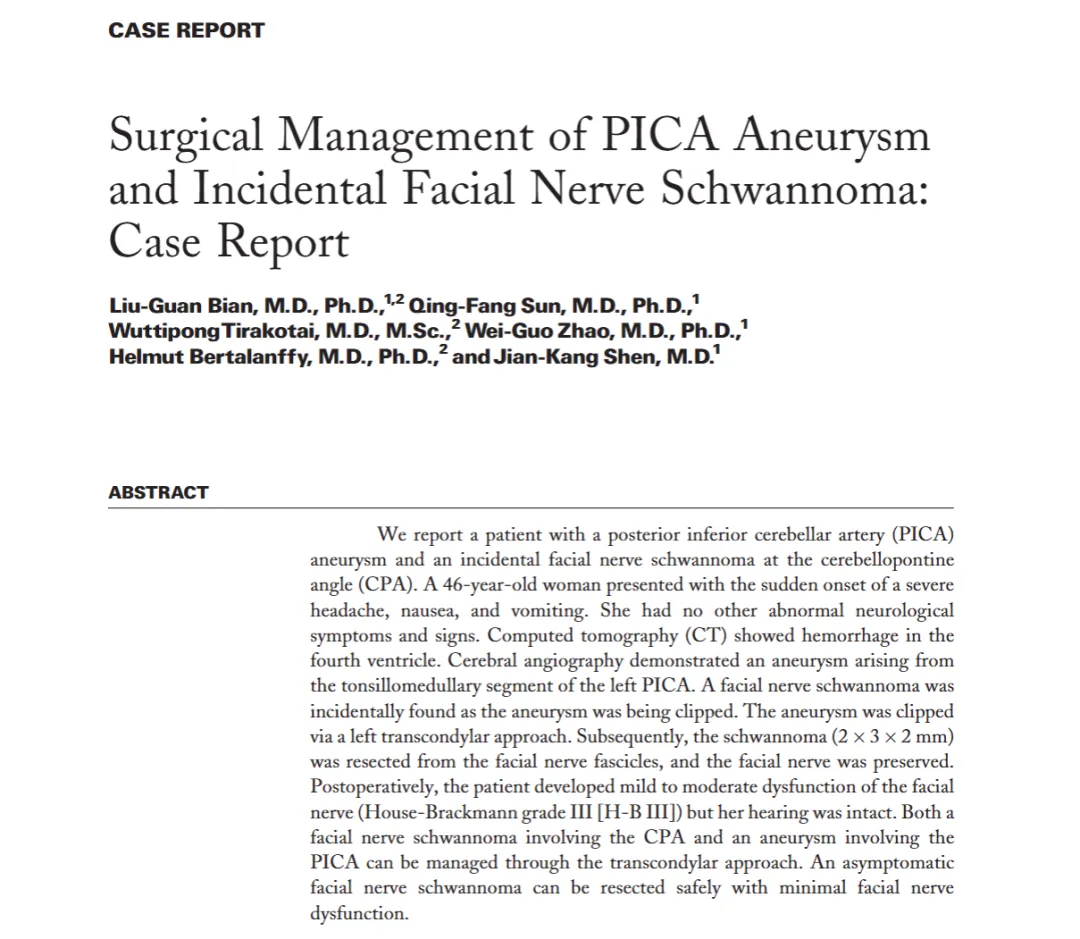

一台原本用于抢救脑出血的急诊手术,竟在术中意外发现了一枚此前毫无症状的隐匿小肿瘤。是冒险一并处理,还是暂且搁置留待观察?...